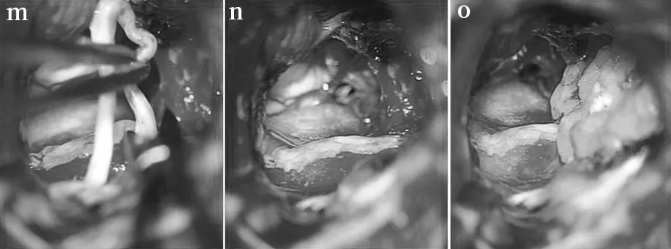

STEP 07:准备合适长度的移植体(m), 并用纤维蛋白胶(n)固定到残端,脂肪用于防止脑脊液泄漏(o)。

随后,巴教授进行了面神经重建术,将2厘米长的腓肠神经移植桥接到健康的面神经内侧和外侧残端,对面神经功能进行重建。术后13天,Elsa得以恢复出院,无任何新发神经功能缺损,更没有出现面瘫、耳聋等严重后果。12个月后的随访检查显示,她的面神经明显恢复。从此,Elsa又可以重展笑容。